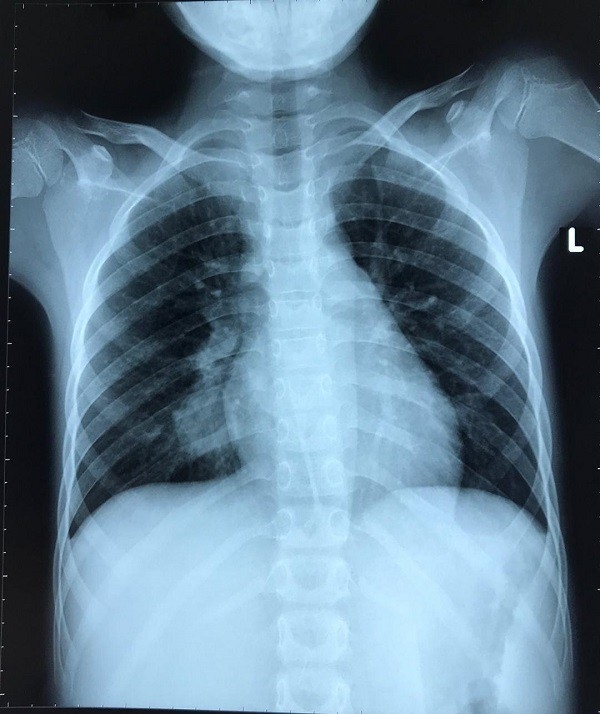

Trước khi nhập viện 2 ngày, bệnh nhi bị đau bụng từng cơn, nôn dịch xanh, vàng. Tại khoa ngoại, qua thăm khám lâm sàng và siêu âm, chụp X-quang ổ bụng, bệnh nhi được các bác sĩ chẩn đoán tắc ruột và phẫu thuật khẩn cấp ngay trong đêm.

Trong quá trình phẫu thuật bác sĩ phát hiện đoạn ruột non của bé có búi tóc rất to, làm tắc nghẽn đường ruột, may mắn chưa có hiện tượng thủng ruột. Một tuần sau mổ, bé gái đã hồi phục và được khám, tư vấn tâm lý trước khi xuất viện.

Theo bác sĩ Nguyễn Hiền, khoa ngoại - Bệnh viện Nhi Đồng 2, bệnh nhân mắc phải hội chứng Rapunzel (Rapunzel là công chúa trong truyện cổ Grim bị mắc kẹt trong ngọn tháp, cô đã thả mái tóc dài của mình qua một cửa sổ của để giúp một hoàng tử leo lên giải cứu) người bệnh thường có biểu hiện ăn chính tóc của mình, hoặc người khác, khiến cho tóc bị rối và mắc kẹt trong dạ dày, ruột lâu ngày gây tắc, thủng ruột.

Bệnh nhân bị mắc hội chứng này thường có biểu hiện đau bụng, buồn nôn, giảm cân nhanh, táo bón, tiêu chảy… Nguyên nhân của bệnh chưa được xác định rõ ràng, có thể là do khiếm khuyết về trí tuệ, rối loạn tâm thần, chấn động tâm lý từ thơ ấu, gặp căng thẳng quá mức hoặc có thể là thiếu sắt hay mắc bệnh celiac.

Bệnh được điều trị chủ yếu bằng phẫu thuật và cần được tư vấn tâm lý, bổ sung vi chất để ngăn ngừa việc ăn tóc xảy ra. Phụ huynh phải tham gia điều trị cùng với bác sĩ để trẻ được hỗ trợ đồng thời cải thiện hành vi tiêu thụ tóc và tinh thần cho trẻ.